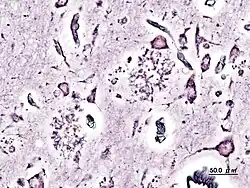

Impregnación argéntica de una biopsia de un paciente afectado de Alzheimer. Se observan placas seniles.

Tradicionalmente, se han empleado técnicas de impregnación de metales para contrastar las preparaciones para microscopía óptica. Las impregnaciones argénticas han sido especialmente precisas, como la de Golgi o Rio Hortega.